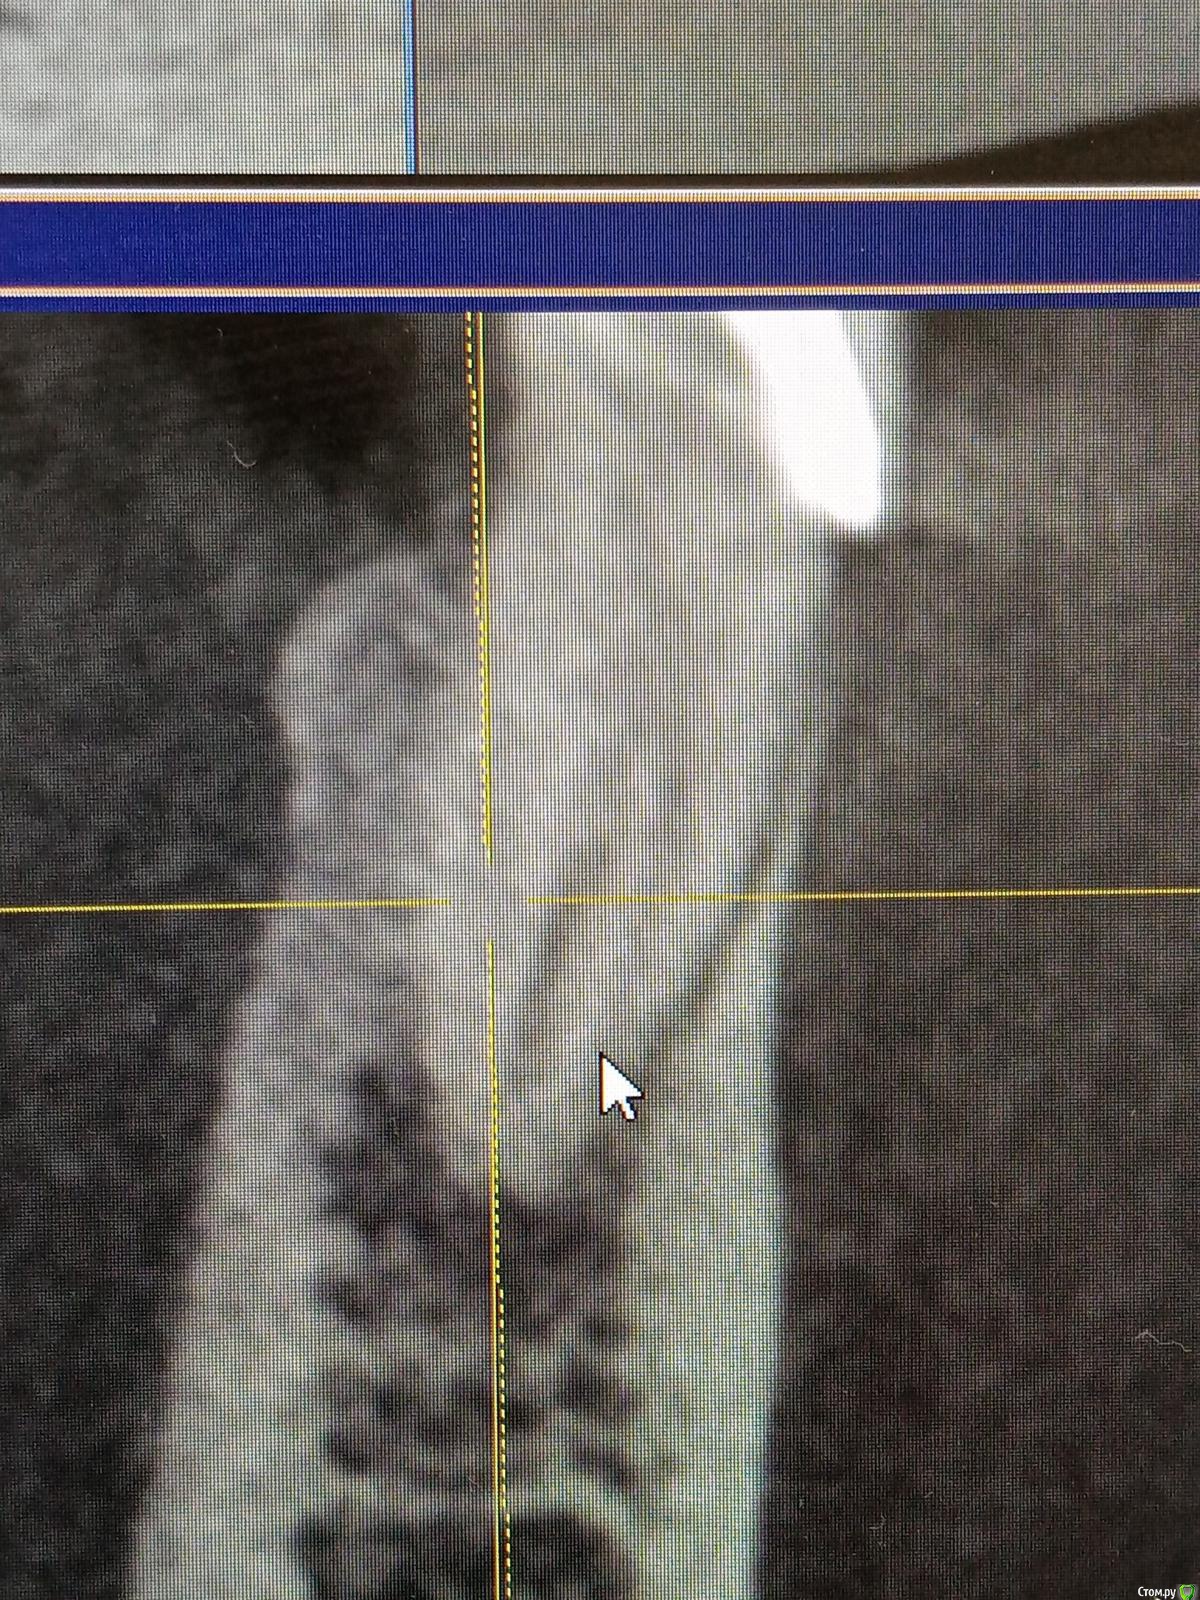

Raimar Опубликовано 30 июня, 2020 Поделиться Опубликовано 30 июня, 2020 Зуб 4.5, ранее лечен, (эндо), пациентка пришла ко мне на перелечивание с острой болью, основную гуттаперча удалил,далее файл упирается, нужно ли пытаться распломбировать маленькие канальцы? Ссылка на комментарий